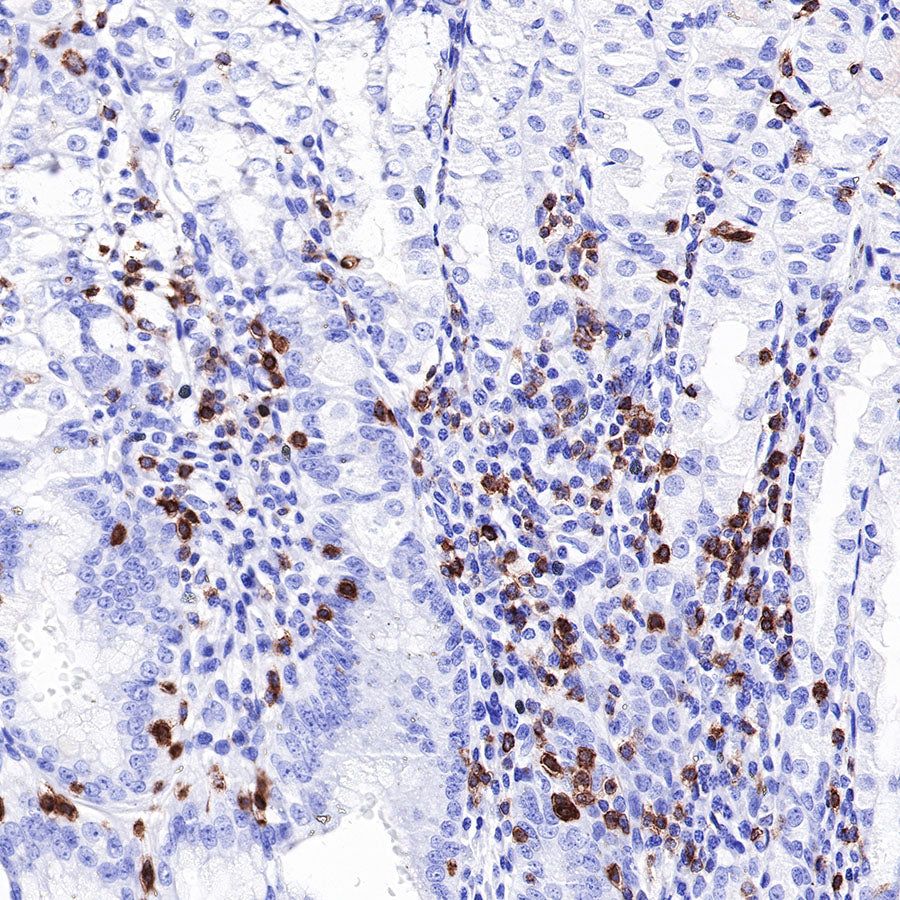

Immunohistochemistry

CD7 is a single-domain Ig superfamily molecule expressed on human T and NK cells, as well as on cells in the early stages of T, B, and myeloid cell differentiation. CD7 is highly expressed on malignant immature T cells and is generally absent on malignant mature T cells [PMID: 10530432]. CD7 is Lymphoid marker, which expressed in 30% of AML cases and linked with poor prognosis in myeloid malignancies [PMID: 21148082].

| IHC-P | 1:1000 | null |